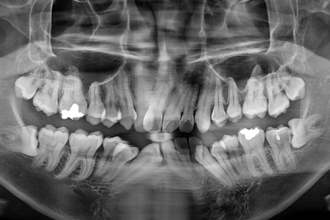

사랑니발치

굿프렌즈 치과 임상 케이스